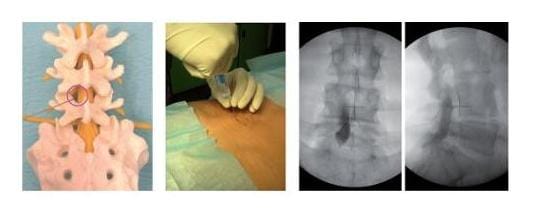

Beispiel einer Injektionsbehandlung bei einem Bandscheibenvorfall

Beispiel einer Injektionsbehandlung bei einem Bandscheibenvorfall.

Wie das Modell links zeigt, wird das Medikament in den Raum um den Spinalkanal injiziert (2. Bild), wo der Bandscheibenvorfall Beschwerden durch Druck auf die Nervenwurzel verursacht. Die Verteilung des Medikamentes wird mit Kontrastmittel durch Röntgen überprüft (rechte Bilder). (Bilder: Orthopädie)